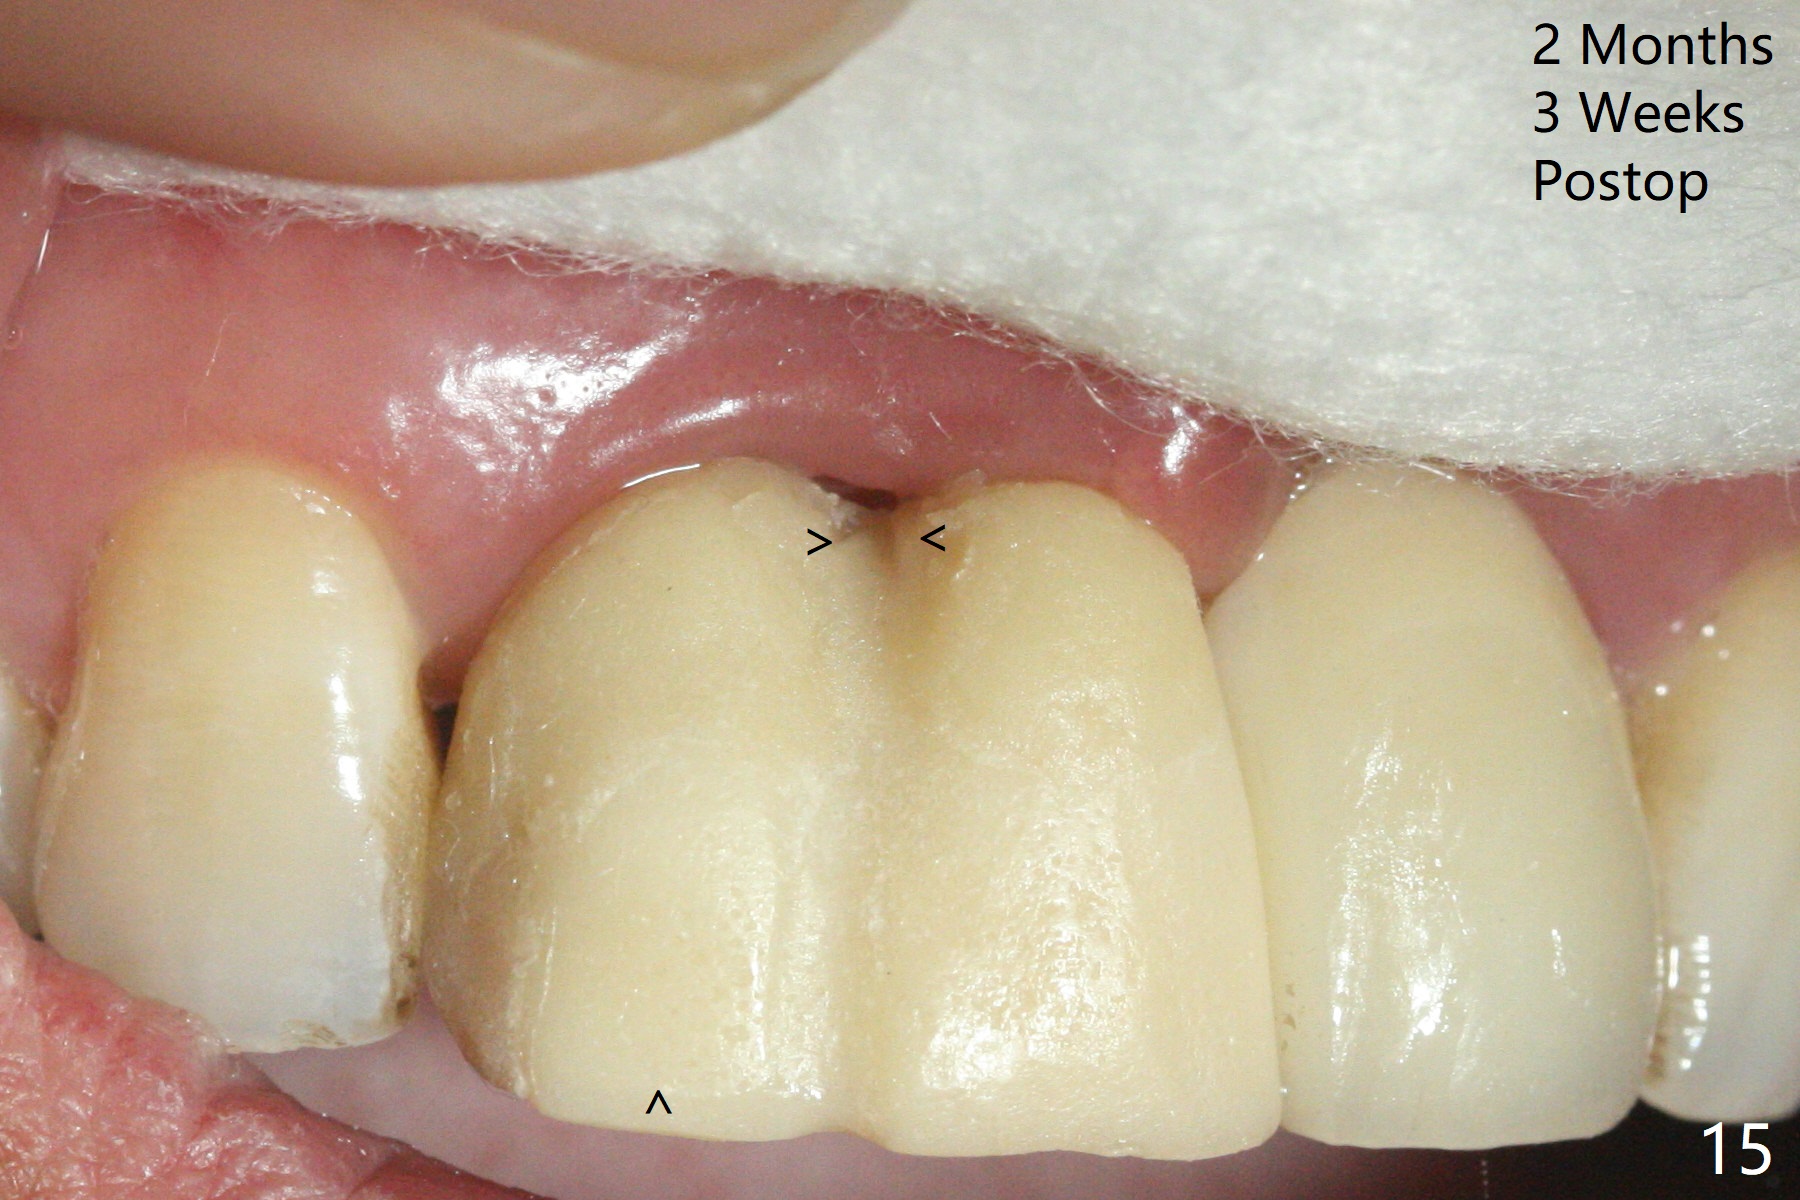

拆除部分桥发现:中,侧切牙牙龈红肿(图一),不利于切口和伤口愈合。不过还是在中切牙区切开,牙龈相当厚,有利于今后牙龈形成凹陷和乳头。坏消息是近远中距离太短,不利于植牙以及今后局部卫生维护,所以决定只在侧切牙种植(图二,三),完成钻洞后,颊侧根尖穿孔植骨,然后植入植体,即刻放置修复基台(图四 (*:牙龈乳头)),暴露基台牙龈缘,制作临时悬臂桥 (图五),两个中切牙牙冠长度差不多,插入临时桥时颊侧牙龈乳头基本形成(图六:*),缝合前颊侧,腭侧牙龈瓣下放置粘性骨块(图七,八:* )和PRF膜(图七:^)。最后使用牙周敷料。但愿术后牙龈炎症消失,形成良好牙龈乳头和pontic concavity。 其实由于口腔卫生习惯,术后十七天颊侧牙龈仍红肿(图九),而腭侧正常。如果口腔卫生改善而红肿依然存在,让实验室制作临时桥。术后一个月颊侧牙龈红肿好些(图十),好像骨粉丢失少许,可能与水枪使用有关。右上1牙冠显得太短(*)。也太肥大,因为右上1切缘太颊侧,与左上1对比(图十一:*)。由于颊侧牙龈(图十二:B)术中推向颊侧,与腭侧(P)牙龈之间放置大量粘性骨粉,术后一个月骨粉(<)形成牙龈,形成凹陷。颊侧萎缩不再明显了。右上1牙冠颈部多加些树脂,牙齿就显得长的多(图十三:箭头)。与侧切牙之间颈部故意留下间隙(*),让牙龈入位(空箭头),形成龈乳头。当右上1临时牙冠切缘(图十四:*)移到腭侧,外形改观不少。下次改善侧切牙唇侧。术后两个月三个星期牙龈红肿好像减轻,牙龈没有进入切牙间隙,干脆用树脂关闭(图十五:> <)。下次减少侧切牙切缘(^),适当增加中切牙长度(上提牙龈)。术后3.5个月植体好像整合,基台完全就位(图十六)。术后3.5个月Pontic凹陷形成,但是1,2之间龈乳头始终无法形成(图十七)。以后类似病例应该多种植一个。此例草率取模,可能需要临时粘固,观察植体近中颊侧所谓瘘道,必要刮治。由于比色不佳,需要实验室颜色更改,病人强化卫生,术后七个月,永久性牙冠粘固前,局部牙龈健康(图十八)。